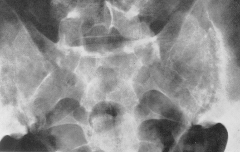

COXARTROZA

forma polara superioara în care se produce îngustarea spatiului articular în partea superioara si osteoscleroza suprafetelor articulare la acelasi nivel cu aparitia de osteofite în partea superioara a sprâncenii cotiloide;

forma polara inferioara cu aceleasi simptome situate însa la partea inferioara a articulatiei;

forma centrala în care capul femural se înfunda în cavitatea cotiloida cu pensare de spatiu si osteoscleroza în oglinda;

forma atrofica în care predomina osteoporoza cu deformari accentuate ale oaselor participante la articulatie.

În stadiile avansate capul femural este turtit deseori luând aspect de ciuperca sau tampon de locomotiva, cu zone de osteoliza în capul femural sau/si în coxal cu osteofite marginale, cu pensarea articulatiei (niciodata nu se produce anchiloza).